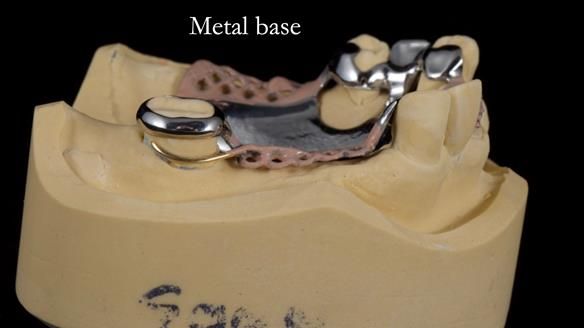

This edition features the case of Edgar, who sought help for a poorly fitting, acrylic-based partial denture that rocked, affected his speech, and caused discomfort. After considering various treatment options, including dental implants, Edgar opted for a metal-based removable partial denture, designed by myself with input from my technician, Rowan Garstang.

Treatment Process: I provided the clinical work while Rowan Garstang delivered the technical aspects. The treatment required fifteen visits to fit and review Edgar.